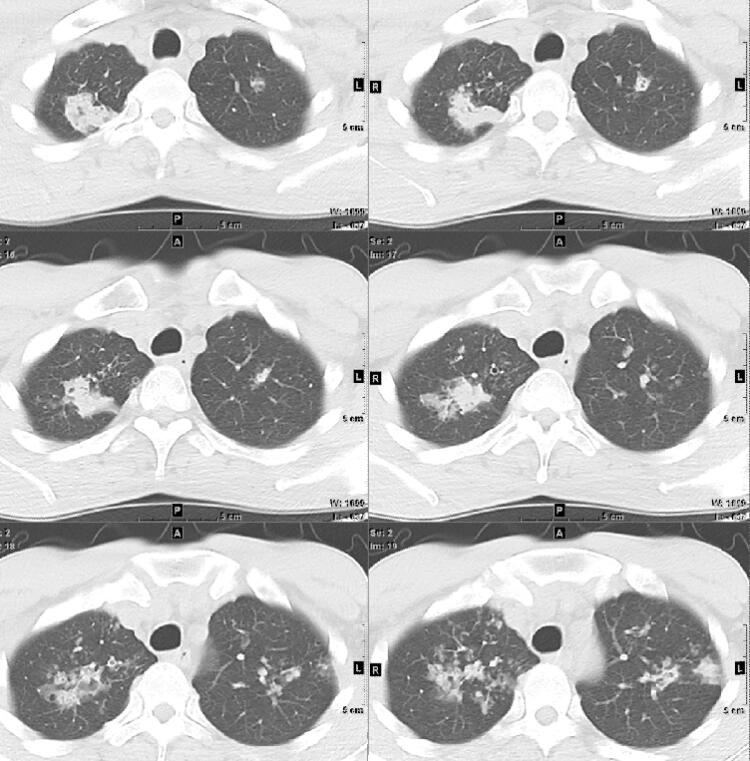

双肺多发结节,斑片,实变影

图片尺寸4096x3072